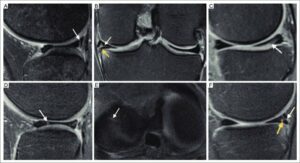

- Knee-MR-imaging-of-types-of-meniscal-tears-A-longitudinal-tear-The-sagittal-FS_W640 © Francisco EspinosaKarla V. Rodriguez-AlanisKarla V. Rodriguez-Alanis is licensed under a CC BY-NC-ND (Attribution NonCommercial NoDerivatives) license